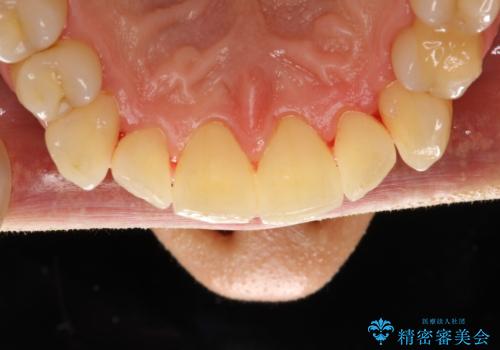

歯磨き中に血が出る PMTCで歯石除去

- 毎日の歯磨きの際に出血する。歯科でにクリーニンングをしばらくしていないとのことでした。PMTC60分コースを行いました。

歯磨きの際の出血は、歯肉炎や歯周病の症状とも言えます。歯周ポケットに歯周病菌が棲みつき、歯周病菌の出す毒素が歯茎に炎症を起こします。炎症が拡大し、歯周組織が破壊されたまま放置すると、最悪の場合、歯を支えている骨が溶かされ、歯がぐらぐらしてきます。